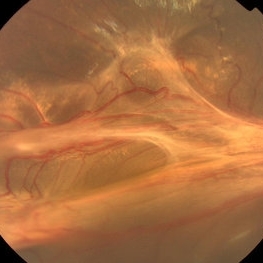

Falciform Retinal Detachment Associated with Toxocariasis (Photo-1)

Falciform Retinal Detachment Associated with Toxocariasis (Photo-1)

Mar 21 2013 by Yusuke Oshima, MD, PhD

Fundus photograph of a 6-year-old boy with a falciform retinal detachment suspiciously associated with toxocariasis.

Photographer: Yusuke Takada, Osaka University Graduate School of Medicine

Falciform Retinal Detachment Associated with Toxocariasis (Photo-2)

Falciform Retinal Detachment Associated with Toxocariasis (Photo-2)

Mar 21 2013 by Yusuke Oshima, MD, PhD

Fundus photograph of a 6-year-old boy with a falciform retinal detachment suspiciously associated with toxocariasis.

Photographer: Yusuke Takada, Osaka University Graduate School of Medicine